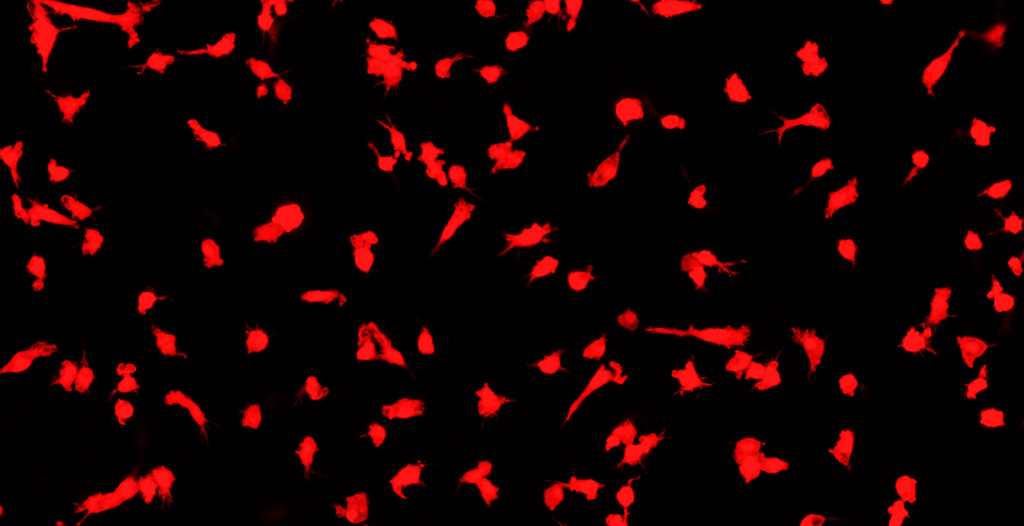

Confocal and super-resolution high content imaging and analysis platforms are used for assessment of effects of neuroinflammation on cellular morphology, for example the morphology of astrocytes and microglia.